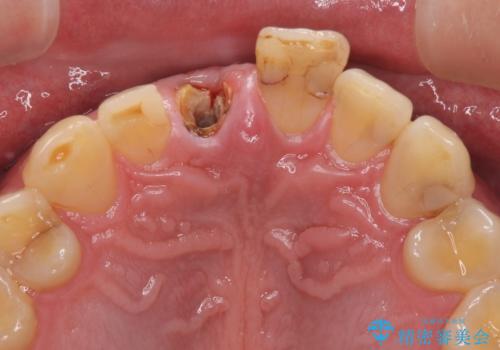

- 前歯の被せものが脱離したとのことで来院された患者様です。

診察の結果、前歯が縦に破折しており、抜歯が必要と診断されました。